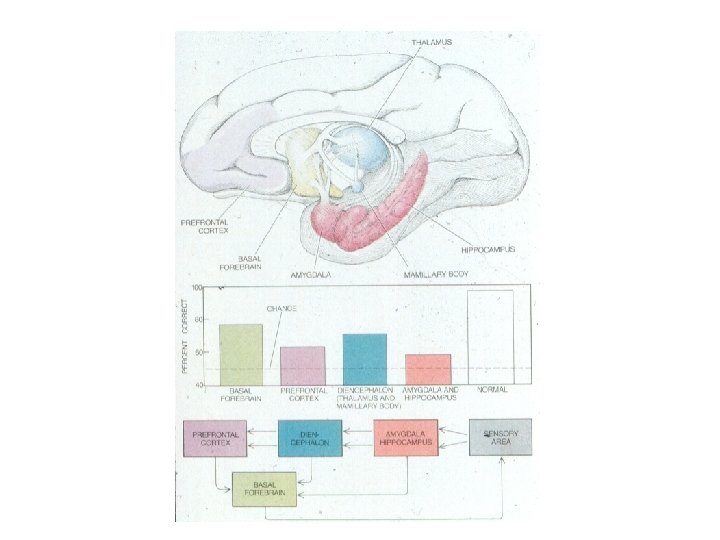

Integrated Circuitry Linking Temporal, Diencephalic, and Basal Forebrain Regions

Zola-Morgan & Squire, 1990

Bauer, Grande, & Valenstein, 2003

Zola-Morgan & Squire, 1990

Key Points • Extended memory system including hippocampus, amygdala, and basal forebrain • We (basically) understand anatomy, now we need to understand computation • Notion of distinct subtypes of amnesia generally less favorable now than 10 years ago • Certain structures are ‘wired’ for associational processing; these structures are reciprocally connected to cortical processors